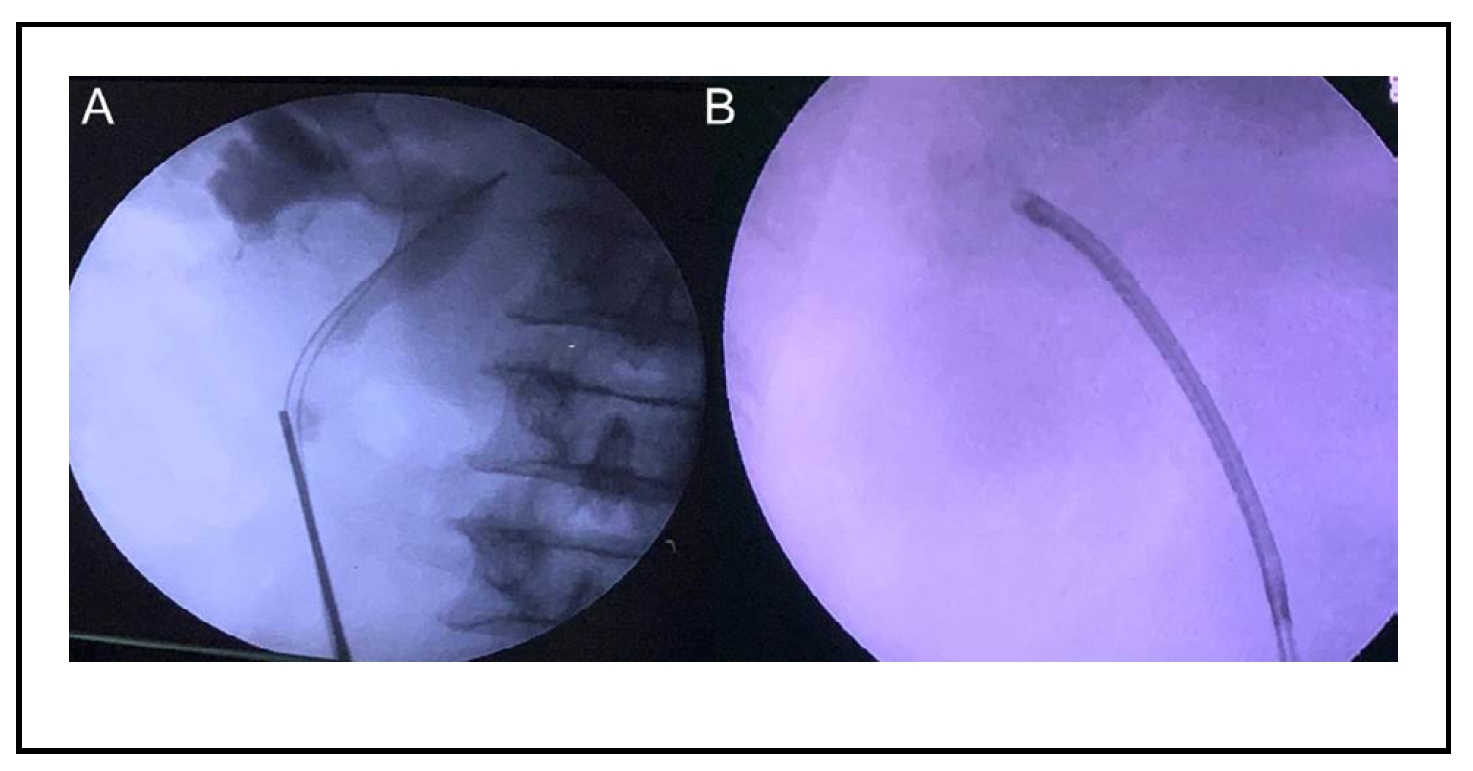

A 45-year-old man presented with 2 months of right flank pain, hematuria, and dysuria. On examination, he was found to have a 15 × 13 mm impacted hard upper ureteral stone (Hounsfield value 1400 HU) just distal to the pelviureteric junction (PUJ). His blood investigations revealed anemia with a hemoglobin (Hb) of 7 g/dL. Rest investigations were normal. Urine culture was sterile. A hematologist's opinion was obtained and he was diagnosed with SCA based on hemoglobin electrophoresis (Figure 1). Under the expert guidance of the hematologist, the patient was transfused with 1 unit of packed cell volume (PCV) and the patient was pre-stented. Two weeks later, his preoperative Hb was 9 g/dL and he was scheduled for RIRS. During RIRS, it was extremely difficult to reach the upper ureteral stone despite pre-stenting. A semi-rigid ureteroscope (6.5/8 Fr) followed by a disposable digital ureteroscope (7.5 Fr) was passed to the level of the upper ureteral stone using two gliding wires (Figure 2A). A thulium fiber laser (IPGTM 35 watt) was used. The upper ureteral stone was first fragmented using laser settings of 0.8-1.0 joules and a frequency of 10-15 hertz. The stone was fragmented from the center to the periphery, safeguarding the ureteral mucosa. Gentle hand-held irrigation with a 100 cm extension tube was used. Once the stone was dis-impacted, it was pushed into the PCS. The ureteral access sheath (10/12 Fr, 35 cm) was then deployed to the upper ureter. A limited-use digital disposable ureteroscope (SeeshenTM) was used for RIRS. The stone was completely dusted into fine golden dust (Figure 2B). Intra renal laser settings were 1.0-1.2 joules and 30-35 hertz for dusting. Finally, popcorn settings of 0.05-0.1 joules and 200 hertz were used. Complete on-table stone clearance was observed. Post-procedure contrast study in the form of retrograde pyelography was normal. A DJ stent (5 Fr/26 cm) was routinely placed. Total ureteroscopy time was 40 minutes. No complications in the form of sepsis or bleeding were noted. The stent was removed after 2 weeks.

Figure 2. (A) Semi-rigid ureteroscope negotiated up to the level of the upper ureteral stone with difficulty with double gliding wire. (B) Complete stone clearance with RIRS.